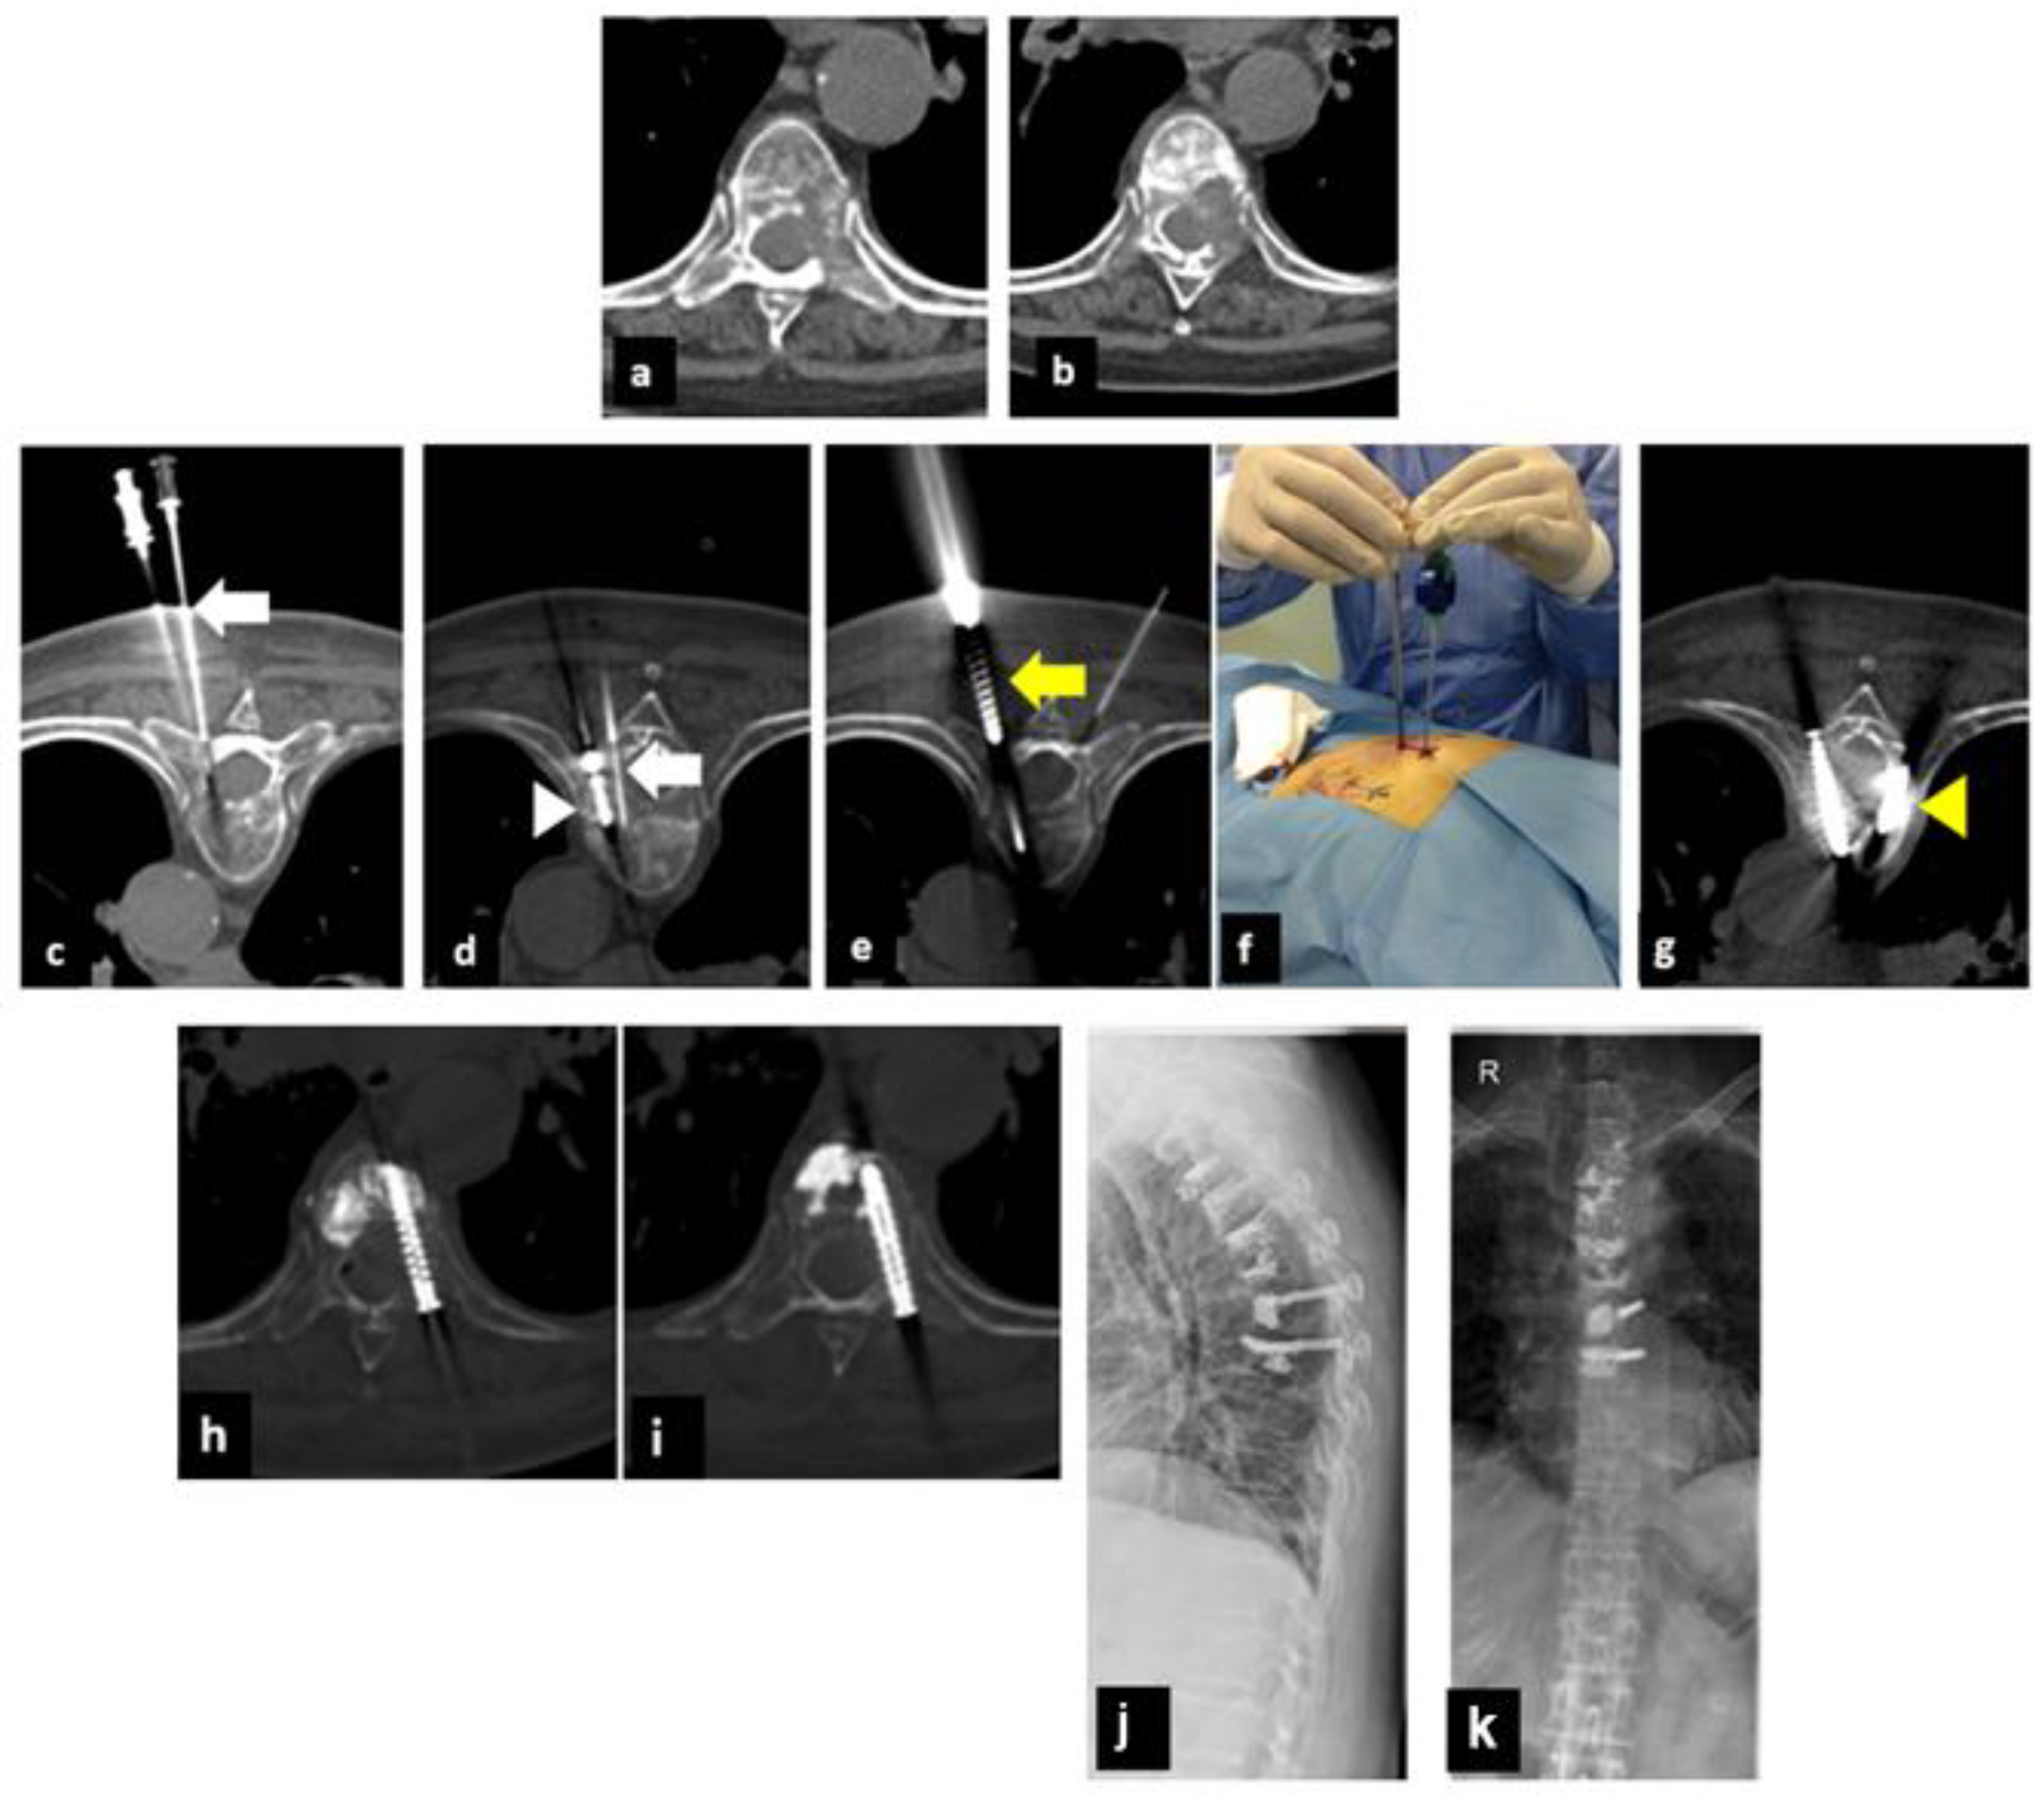

2. Materials and Methods

2.1. Treatment Technique

| 3 | 70 | NSCLC | D8–D9 | 2 | 2 | 6/4 | 1/2 | 1/1 |

| 4 | 67 | NSCLC | D7–D8 | 2 | 2 | 7/2 | 2/1 | 0/1 |